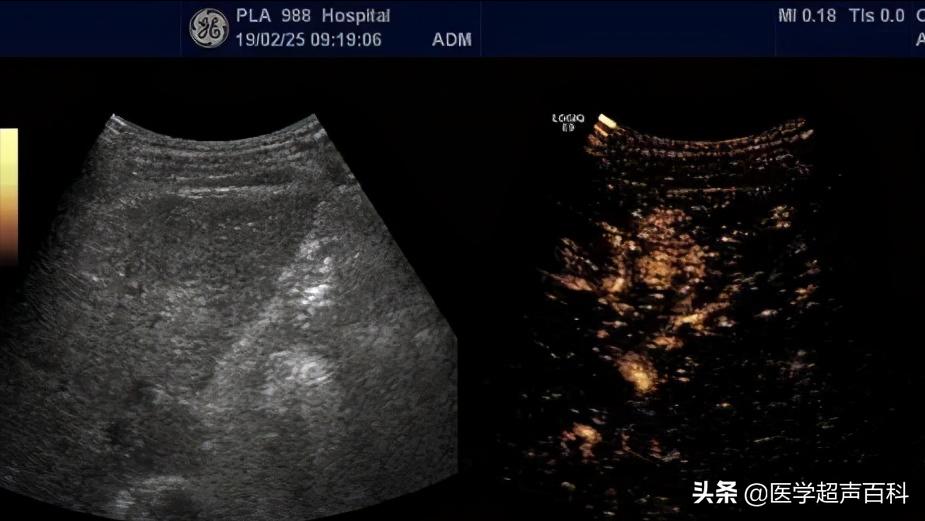

彩超主要观察肝血管血流,门静脉有无返流,侧支循环是否开放,如附脐静脉、胃冠状静脉、胃底静脉、脾肾静脉等,只要开放,就说明有肝门静脉高压,要特别注意饮食时,不吃鱼刺,鸡碎骨,以防划破食道静脉引起大出血,甚至死亡。

慢性肝病要求三个月查一次超声,目的一是了解肝质地情况,更重要的是监测早期肝癌的出现,早期微小肝癌在 1-2cm 就已被能发现,对早期治疗意义重大,如在检查中发现了异常结节,经超声造影甚至活检,可以很快确定是否是肝癌,早期微小肝癌不管是手术还是介入,疗效都相当不错,存活 5 年、8 年已是很常见,甚至可完全治愈。